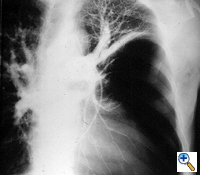

| Figure 3: Chest x-ray of a large bulla with true infection; after the appropriate medical treatment fever, hemptysis and fluid level persisted and the bulla was resected. |

Surgery is generally indicated to modify the functional status of the underlying lung by (1) relieving restrictive changes; (2) increasing compliance and airway caliber; (3) improving V/Q ratio; and (4) decreasing the physiologic dead space. These goals are easy to obtain in patients with enlarging bullae and minimal underlying lung disease. These are the best candidates for surgery and optimal results can be expected. Surgery is also indicated to treat complications related to the bullae, such as pneumothorax, true infection (Figure 3), hemoptysis, cancer (Figures 4, 5), and pain.